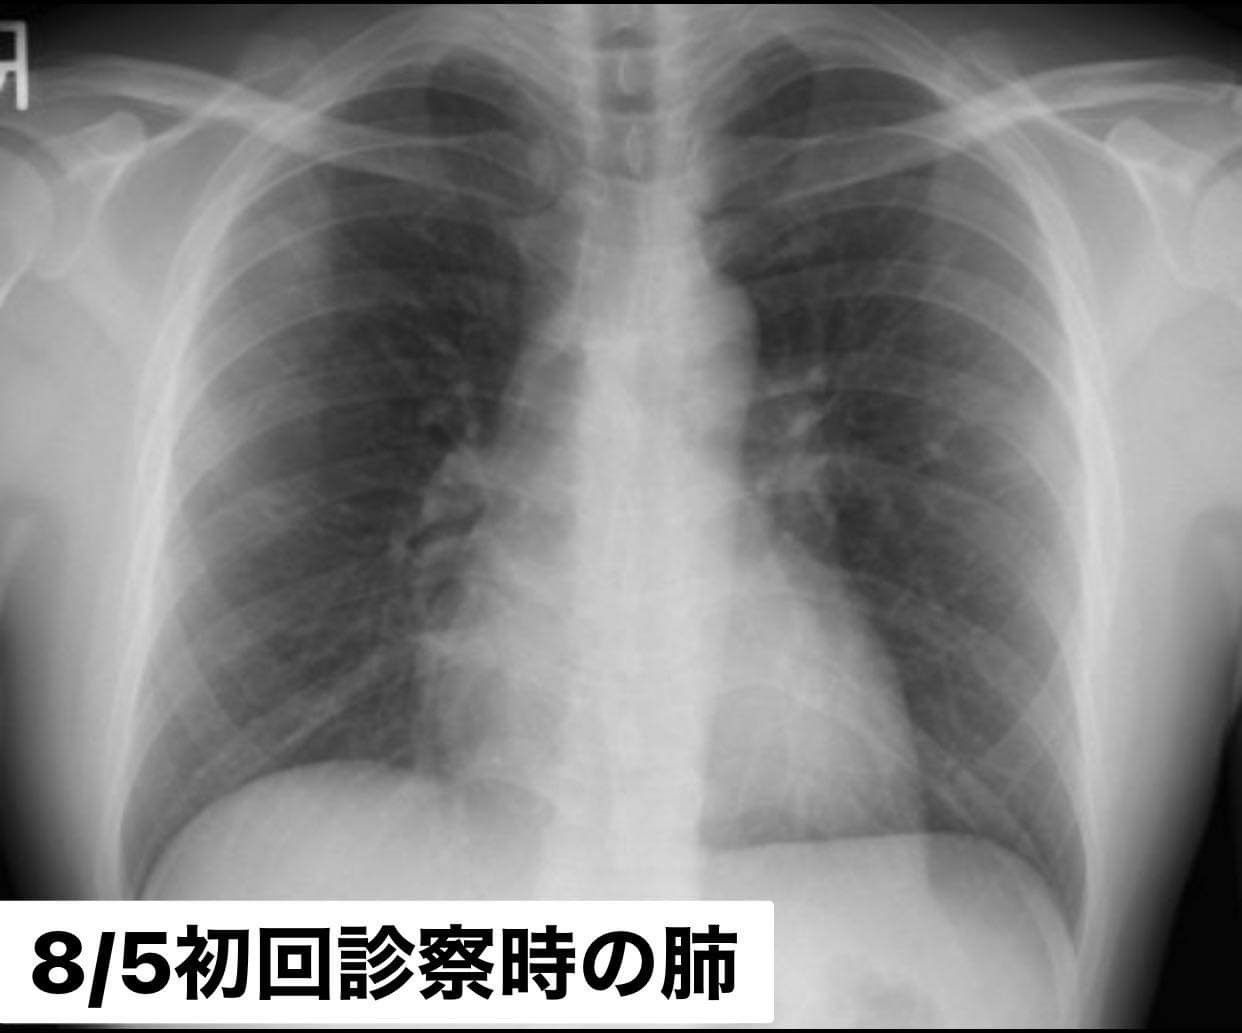

8月5日、「東京都発熱相談センター」で紹介された病院でのレントゲン写真。まだ肺はキレイだった(写真:取材者提供)